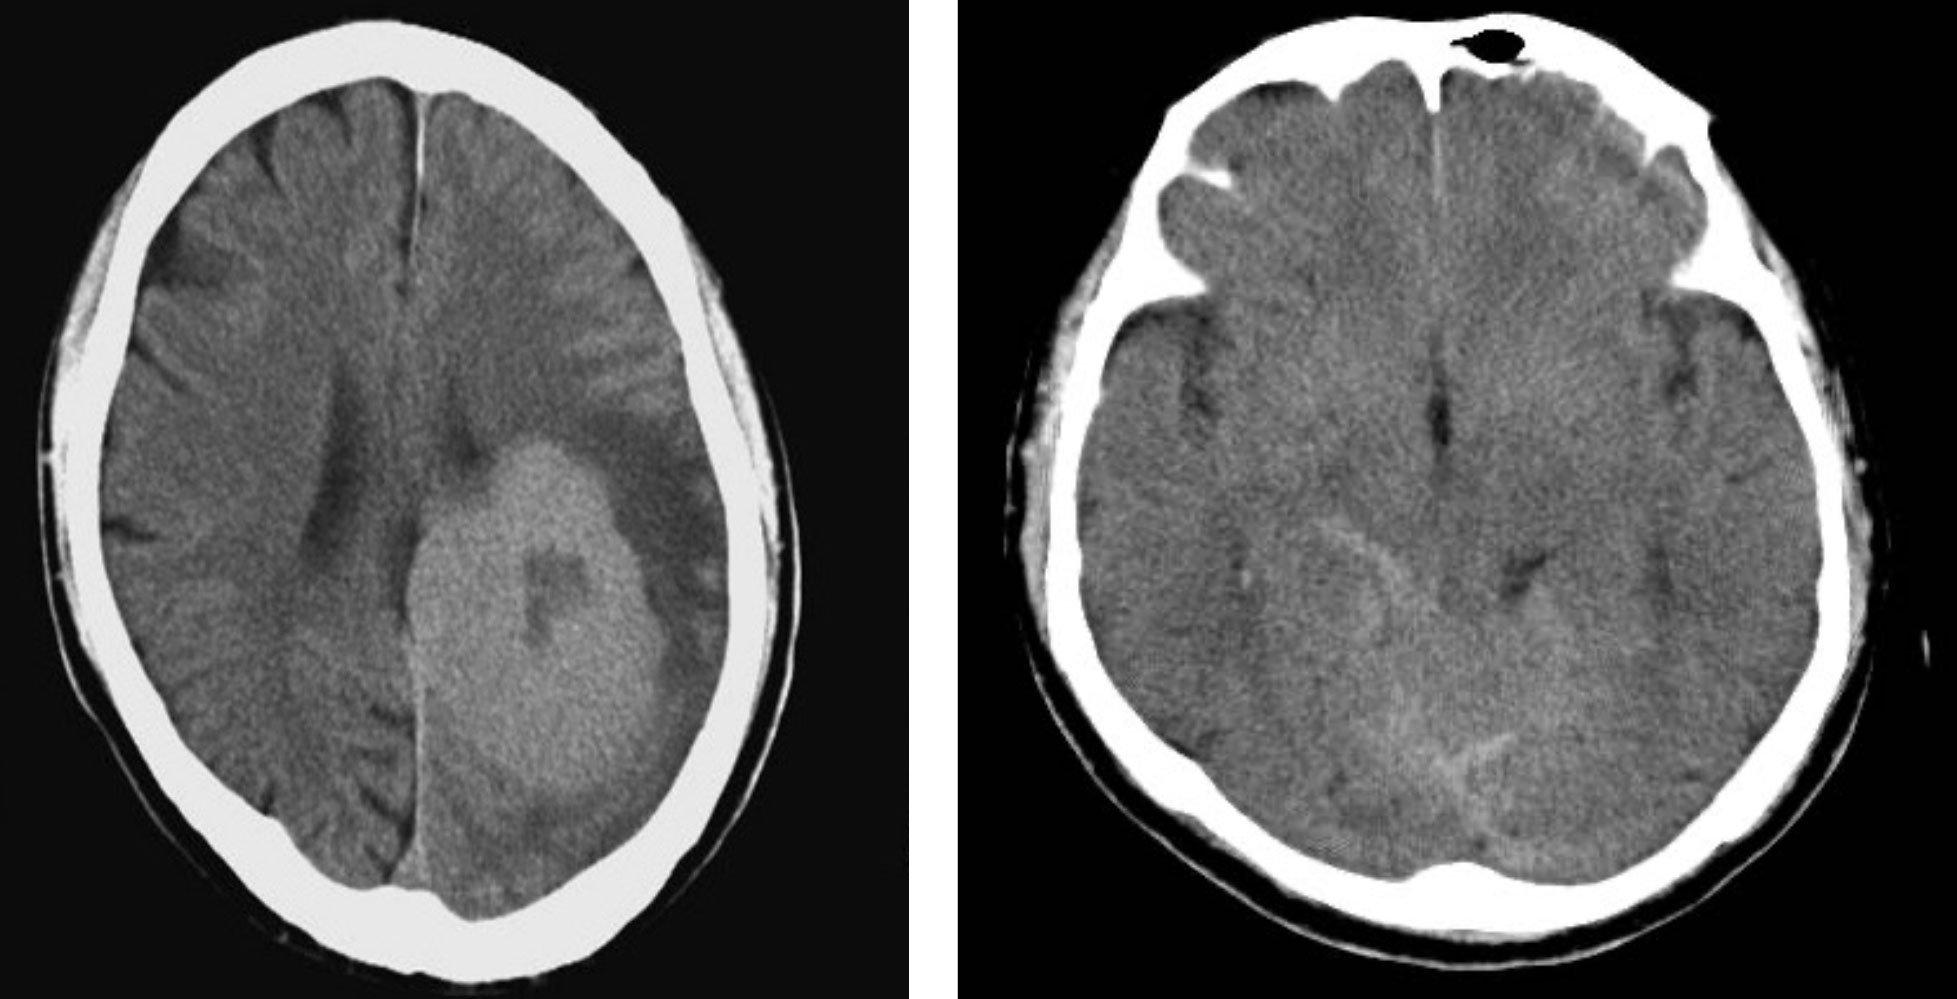

ショップレビュー ランキング 尾尻博也, | 第3版 頭頸部のCT・MRI 酒井 Amazon | 通販 | |本 修 健康・医学の詳細情報

頭頸部のCT・MRI 第3版 | 尾尻博也, 酒井 修 |本 | 通販 | Amazon。MEDSi)株式会社 メディカル・サイエンス・インターナショナル。頭頚部 CT : 正常解剖学 | e-Anatomy。フライドガーリック粒 にんにく ニンニク 500g 1袋。頭部 | ページ 2。頸部リンパ節のレベルシステムとMRI横断像の関係。頭部CT検査 | オリエンタル蒲郡健診センター。Philips - dStream Sentinelle Breast 16ch HCNMRF465 MR coil。。頭頚部 CT: 正常解剖学 | e-Anatomy。頭頚部 CT: 正常解剖学 | e-Anatomy。咽頭扁桃 - e-Anatomy - IMAIOS。なんせい動物病院/CT・MRIセンター | コラム。MRI検査 | 埼玉メディカルセンター | 地域医療機能推進機構。裁断済み、一部マーカー引いてあります。